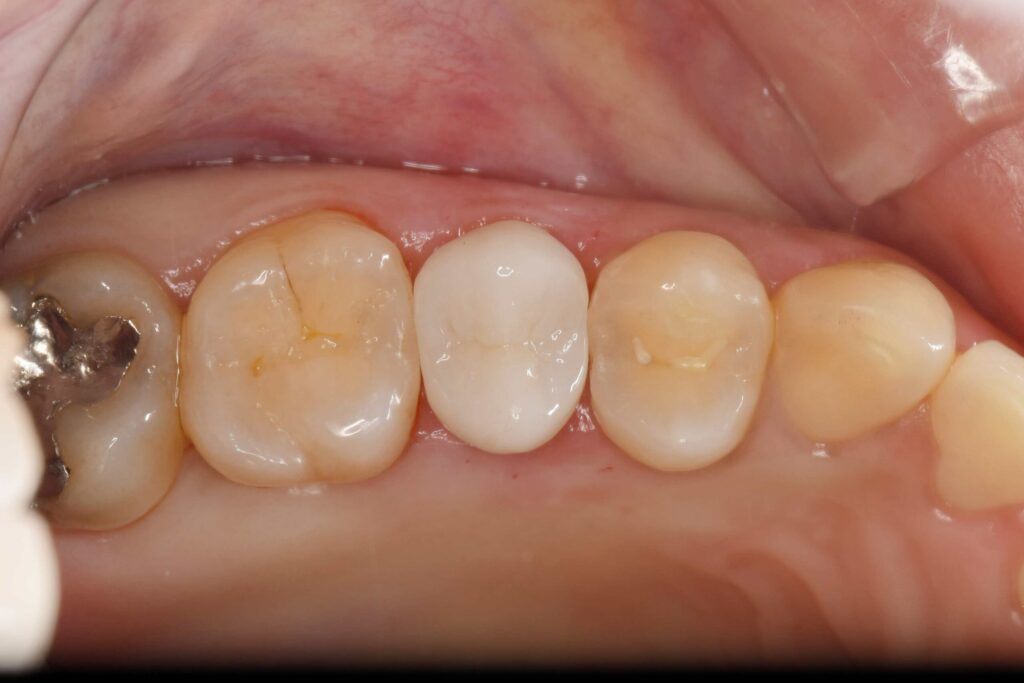

神経保護処置後です。ここから1ヶ月痛みがないかの経過観察を行い、問題がなければ被せ物の処置に移行していきます。

被せ物の試適です。隙間がないことが確認できたため接着を行いました。